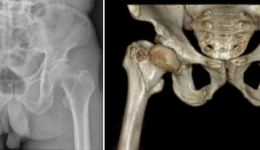

“康复速度真快!做完手术第二天,我就能在医生的帮助下活动,对受伤的髋关节进行功能锻炼了。”近日,不慎从高处坠落、导致两处严重骨折伤市民梁先生(化名)在茂名市人民医院创伤骨科天玑骨科手术机器人的辅助治疗下,顺利地恢复了健康。对于骨科...